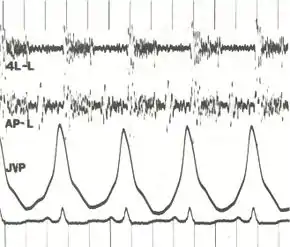

Other typical signs of pulmonary hypertension include an accentuated pulmonary component of the second heart sound, a right ventricular third heart sound, and parasternal heave indicating a hypertrophied right ventricle. Signs of systemic congestion resulting from right-sided heart failure include jugular venous distension, ascites, and hepatojugular reflux.[11][12][15] Evidence of tricuspid insufficiency and pulmonic regurgitation is also sought and, if present, is consistent with the presence of pulmonary hypertension.[11][12][16]

.jpg.webp)

In terms of the diagnosis of pulmonary hypertension, it has five major types, and a series of tests must be performed to distinguish pulmonary arterial hypertension from venous, hypoxic, thromboembolic, or unclear multifactorial varieties. PAH is diagnosed after exclusion of other possible causes of pulmonary hypertension.[12]

Echocardiography

If pulmonary hypertension is suspected based on the above assessments, echocardiography is performed as the next step.[11][12][55] A meta-analysis of Doppler echocardiography for predicting the results of right heart catheterization reported a sensitivity and specificity of 88% and 56%, respectively.[57] Thus, Doppler echocardiography can suggest the presence of pulmonary hypertension, but right heart catherization (described below) remains the gold standard for diagnosis of PAH.[11][12] Echocardiography can also help to detect congenital heart disease as a cause of pulmonary hypertension.[11]

Although pulmonary arterial pressure (PAP) can be estimated on the basis of echocardiography,[62] pressure measurements with a Swan-Ganz catheter inserted through the right side of the heart provide the most definite assessment.[42] Pulmonary hypertension is defined as a mean PAP of at least 20 mm Hg (3300 Pa) at rest, and PAH is defined as precapillary pulmonary hypertension (i.e. mean PAP ≥ 20 mm Hg with pulmonary arterial occlusion pressure [PAOP] ≤ 15 mm Hg and pulmonary vascular resistance [PVR] > 3 Wood Units).[55] PAOP and PVR cannot be measured directly with echocardiography. Therefore, diagnosis of PAH requires right-sided cardiac catheterization. A Swan-Ganz catheter can also measure the cardiac output; this can be used to calculate the cardiac index, which is far more important in measuring disease severity than the pulmonary arterial pressure.[11][63] Mean PAP (mPAP) should not be confused with systolic PAP (sPAP), which is often reported on echocardiogram reports. A systolic pressure of 40 mm Hg typically implies a mean pressure of more than 25 mm Hg. Roughly, mPAP = 0.61•sPAP + 2.[64]